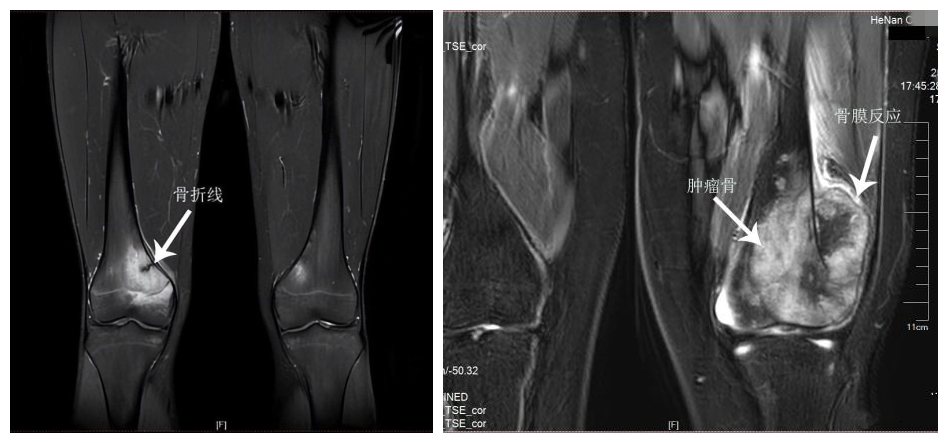

疲劳骨折是发生在高强度、持续性的剧烈运动后的一种慢性骨折和修复过程,多见于长时间的行军,因此又叫「行军骨折」,常见的骨折部位包括股骨、胫骨、跖骨等承重骨。主要表现为骨髓水肿、骨膜反应和骨折线。

2. 影像学检查

二者都有典型的骨髓水肿和骨膜反应性增生,但疲劳骨折大部分可以发现典型的骨折线,恶性骨肿瘤存在诸如皮质骨破坏、瘤骨形成、「Codman 三角」等改变。病人家属可以到相应的专科医院来进行咨询和鉴别。